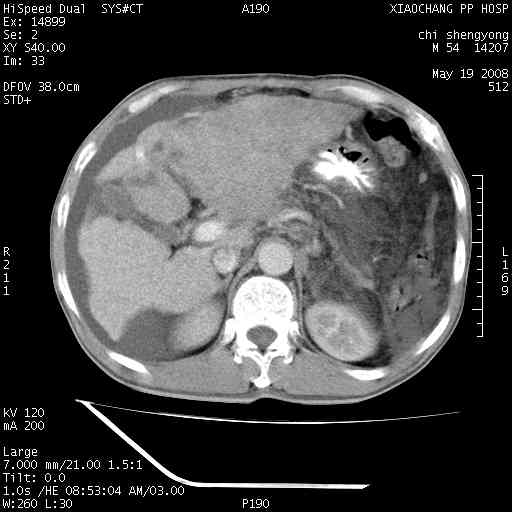

以下是引用zjzjr在2008-5-21 10:52:00的发言:[br]肝左叶巨块型肝癌伴门静脉左支瘤栓形成.肝硬化、腹水,胃底静脉曲张,脾术后改变。

以下是引用随光逐影在2008-5-21 16:20:00的发言:[br]1)肝左叶肝癌伴门静脉左支瘤栓形成,腹膜后淋巴结转移。2)肝硬化、腹水、胃底静脉曲张。3)胆囊炎。4)脾脏缺如,为切除术后所致。